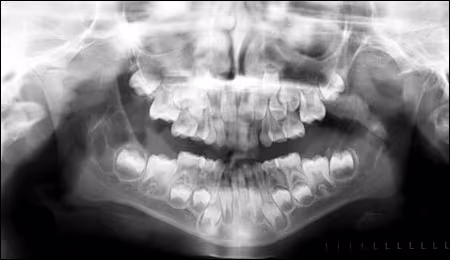

Follow-up three months later (Figure 2) demonstrated the lesions to be fairly stable with perhaps slight enlargement of the lesion on the right.

Figure 2. Panoramic radiograph taken three months following Figure 1 in March 2005

Six months later (Figure 3) the lesion on the right side appeared stable, but the lesion in the left ramus area was now becoming more clearly defined with a multilocular pattern.

Figure 3. Panoramic radiograph taken in September 2005.